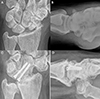

![]() |

Figure 8 Clinical case of Capitolunate Fusion. A and B. Preoperative wrist X-rays of SNAC stage II (AP and Lateral views). C and D. Postoperative wrist X-rays (AP and Lateral views) after 4.7 years. Source: Dr. Emmanouil Apergis. |